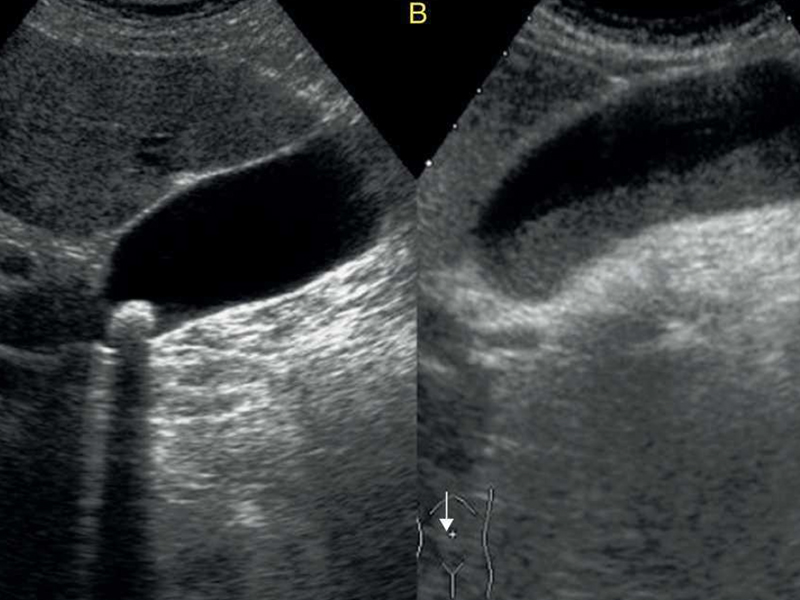

Vesicula biliar con cálculos

(Colecistectomía Laparoscópica)

Cuando la vesícula biliar tiene cálculos, pueden presentarse dolores abdominales que pueden manejarse de forma conservadora, hasta requerir de una cirugía.

• Cálculos en la vesícula, cuando hay síntomas (Colelitiasis)

• Inflamación de la vesícula (Colecistitis)